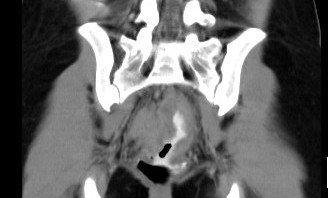

Abdominal CT images

CT finding : Circumferential rectal wall thickening-> Tissue diagnosis -> Rectal cancer

CT finding correlated with plain abdominal radiograph